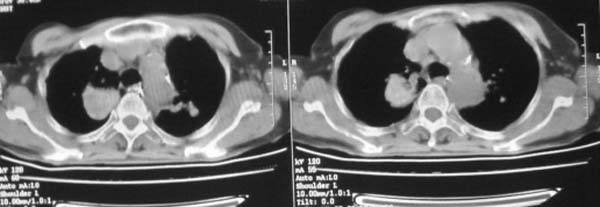

女,78岁,声嘶月余,否认有既往病史,有粉尘接触史10年。

多考虑尘肺,肿瘤性病变不除外

尘肺合并肺癌。

肺癌伴纵膈、双颈部淋巴结转移;尘肺。

考虑肺癌伴纵膈、双颈部淋巴结转移;